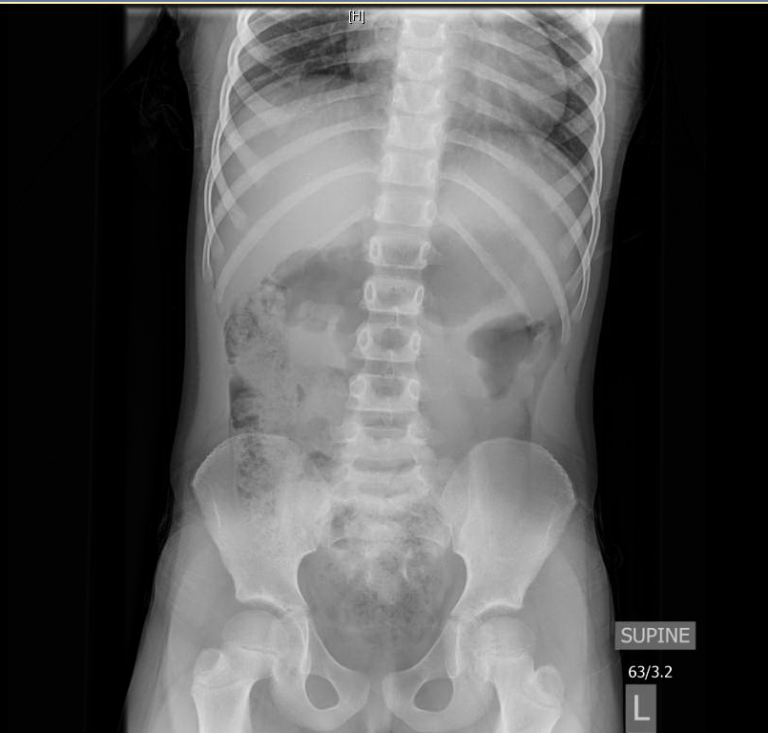

Intussusception Cat X Ray . Diagnosis of intussusception can be. Luminal distention is greater than 2 times normal (4 to 5 times the width of a rib). Causes include mechanical obstruction (e.g., foreign body, intussusception, mass). The presenting signs in dogs and cats with intussusception are varied and nonspecific. Survey radiographs may reveal area of obstruction, such as a tubular soft tissue mass, or gas highlighting area of intussusception. Involves 1 to 3 loops. The intussusception was within the right lower abdomen, and in retrospect likely represents the soft tissue density on the abdominal radiograph as. Functional ileus and severe focal enteritis are possible but less common. This finding along with the clinical signs suggests the presence of an intussusception.

Intussusception Cat X Ray This finding along with the clinical signs suggests the presence of an intussusception. The presenting signs in dogs and cats with intussusception are varied and nonspecific. This finding along with the clinical signs suggests the presence of an intussusception. Functional ileus and severe focal enteritis are possible but less common. Involves 1 to 3 loops. Diagnosis of intussusception can be. Survey radiographs may reveal area of obstruction, such as a tubular soft tissue mass, or gas highlighting area of intussusception. Luminal distention is greater than 2 times normal (4 to 5 times the width of a rib). Causes include mechanical obstruction (e.g., foreign body, intussusception, mass). The intussusception was within the right lower abdomen, and in retrospect likely represents the soft tissue density on the abdominal radiograph as.

GP Refresh Small Animal Radiology Intussusception Cat X Ray Diagnosis of intussusception can be. Causes include mechanical obstruction (e.g., foreign body, intussusception, mass). Involves 1 to 3 loops. Functional ileus and severe focal enteritis are possible but less common. The presenting signs in dogs and cats with intussusception are varied and nonspecific. The intussusception was within the right lower abdomen, and in retrospect likely represents the soft tissue density. Intussusception Cat X Ray.